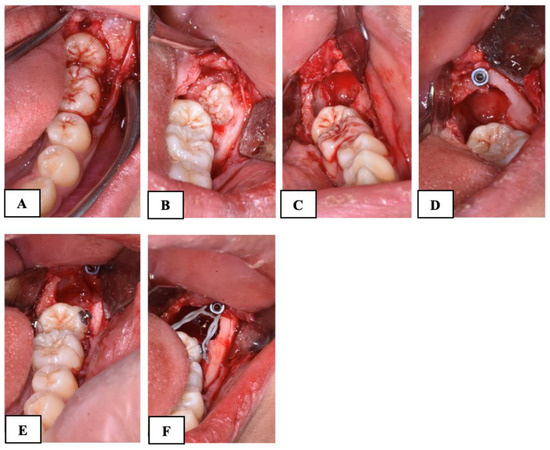

A mucoperiosteal flap was elevated without releasement incisions, which extended from the mandibular first molar to the retromolar area on both the buccal and lingual sides. In all the patients of both groups, the procedure involved the exposure of the crown of MM2 and germectomy of the third molar. In the subjects treated with the traditional technique (Group A), a gentle luxation of MM2 was performed and a 0.6 mm double-twisted brass wire was inserted under the contact point between the first and second mandibular molars (Figure 2).

Figure 2. Surgical procedure with brass wire used in Group A subjects. (A): mucoperiosteal flap and the exposure of the impacted second molar; (B): the exposure of the third molar; (C): the germectomy of the third molar; (D): the application of brass wire; (E): suture.